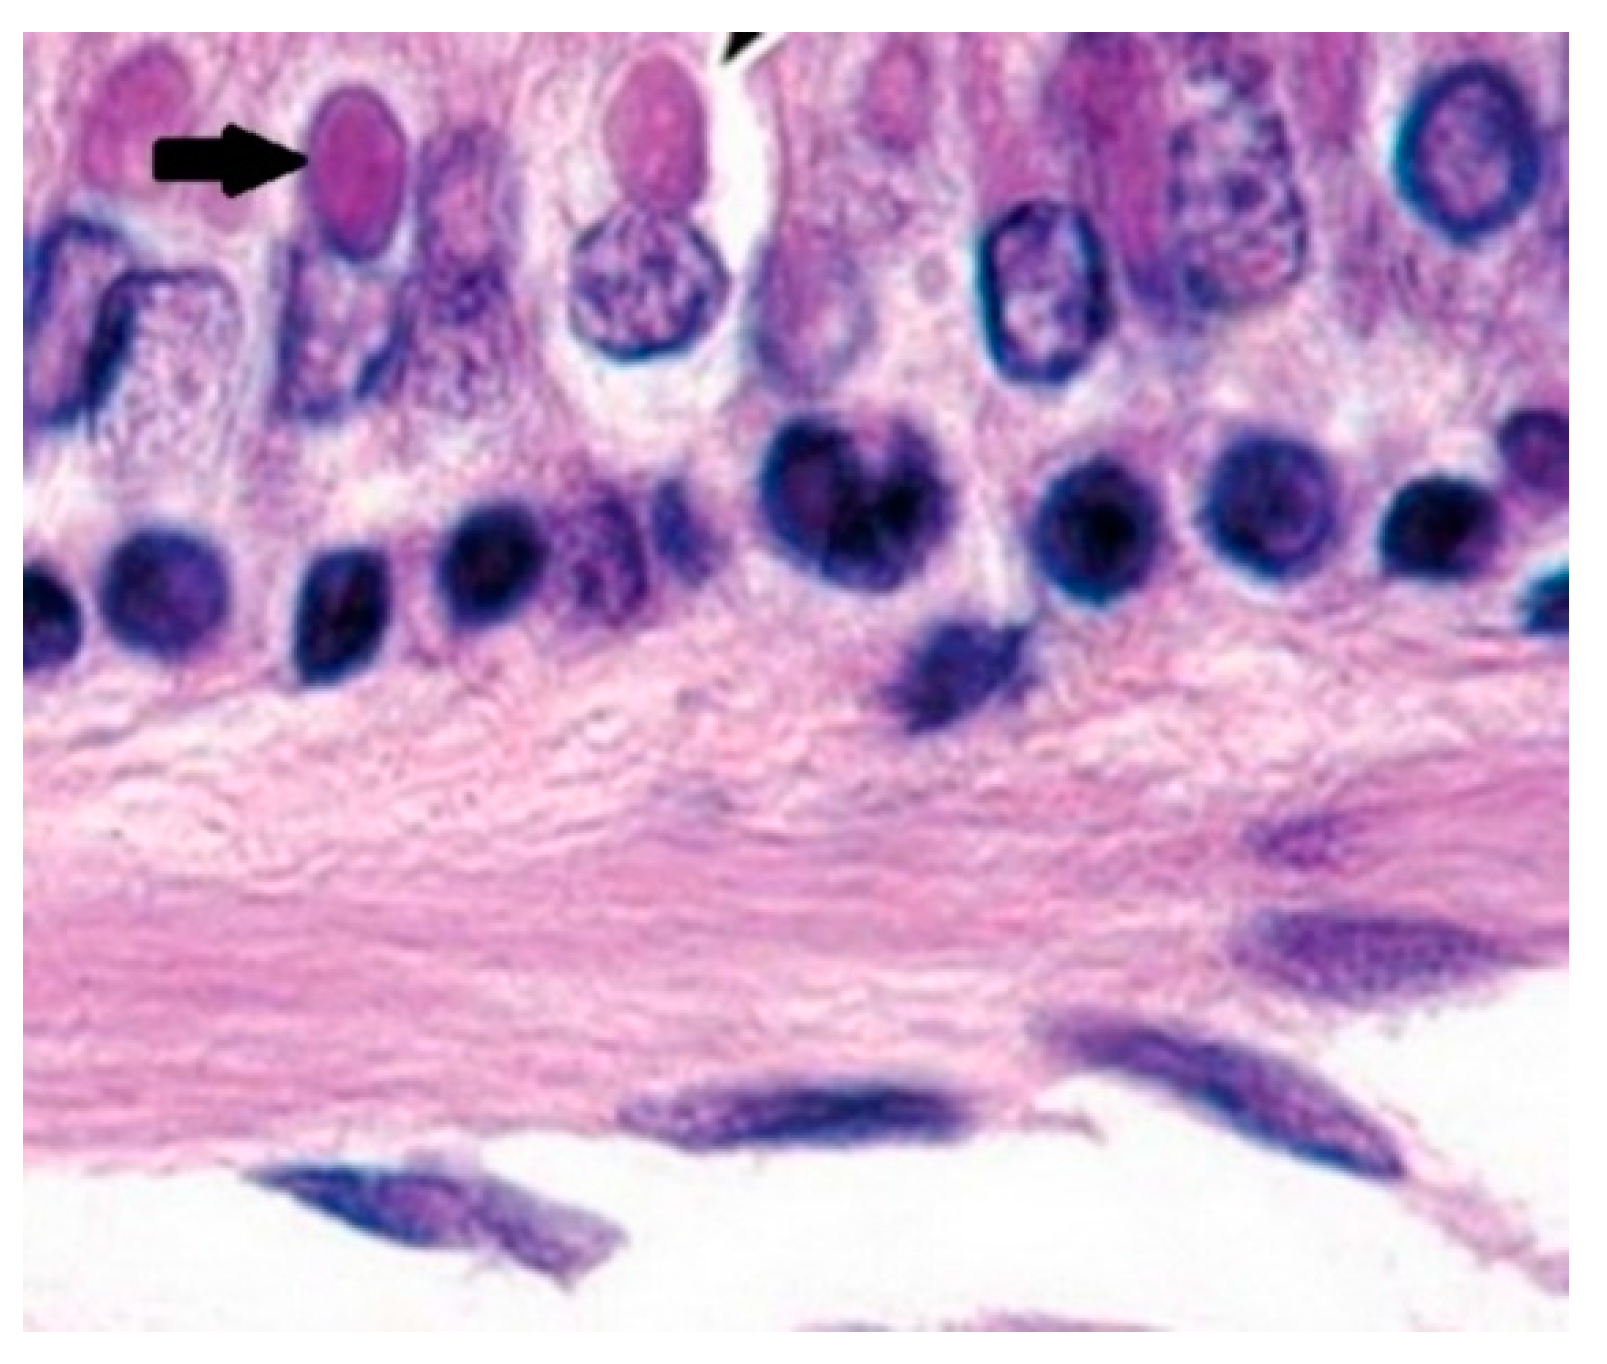

3.6. Immunohistochemical / histopathological examination

3.7. The electron-microscopic examination